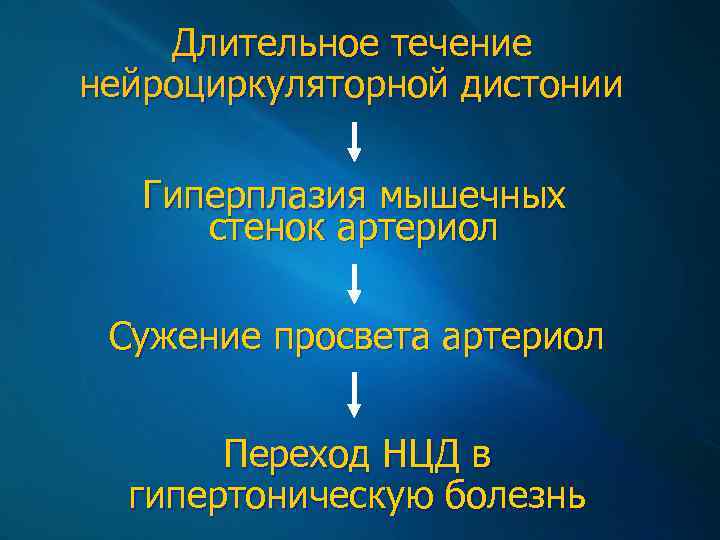

Длительное течение нейроциркуляторной дистонии Гиперплазия мышечных стенок артериол Сужение просвета артериол Переход НЦД в гипертоническую болезнь